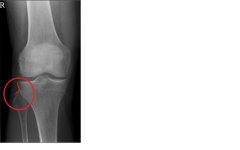

Jedoch habe ich noch Probleme im Gelenkspalt des Schien- / und Wadenbein (müsste das Tibiofibulargelenk sein).

Die OP am vorderen Kreuzband erfolgte im April 2011. Aufgrund der immer noch anhaltenden Schmerzen im Außenbereich des Knies wurde mein Meniskus 2012 genäht (was nichts gebracht hat). Da der Schmerz immer noch vorhanden war entschied ich mich 2014 nochmals für eine Athroskopie (rezension des außenmeniskus, was aber ebenfalls nichts brauchte). Demnach ist an meinem Knie meiner Meinung nach (zumindest aus medizinischer Sicht) nichts mehr zu machen.Jetzt zum Problem: Mit dem Fußball spielen habe ich aufgrund des "Stop&go´s" aufgehört. Seit dem letzten Jahr betreibe ich Triathlon.